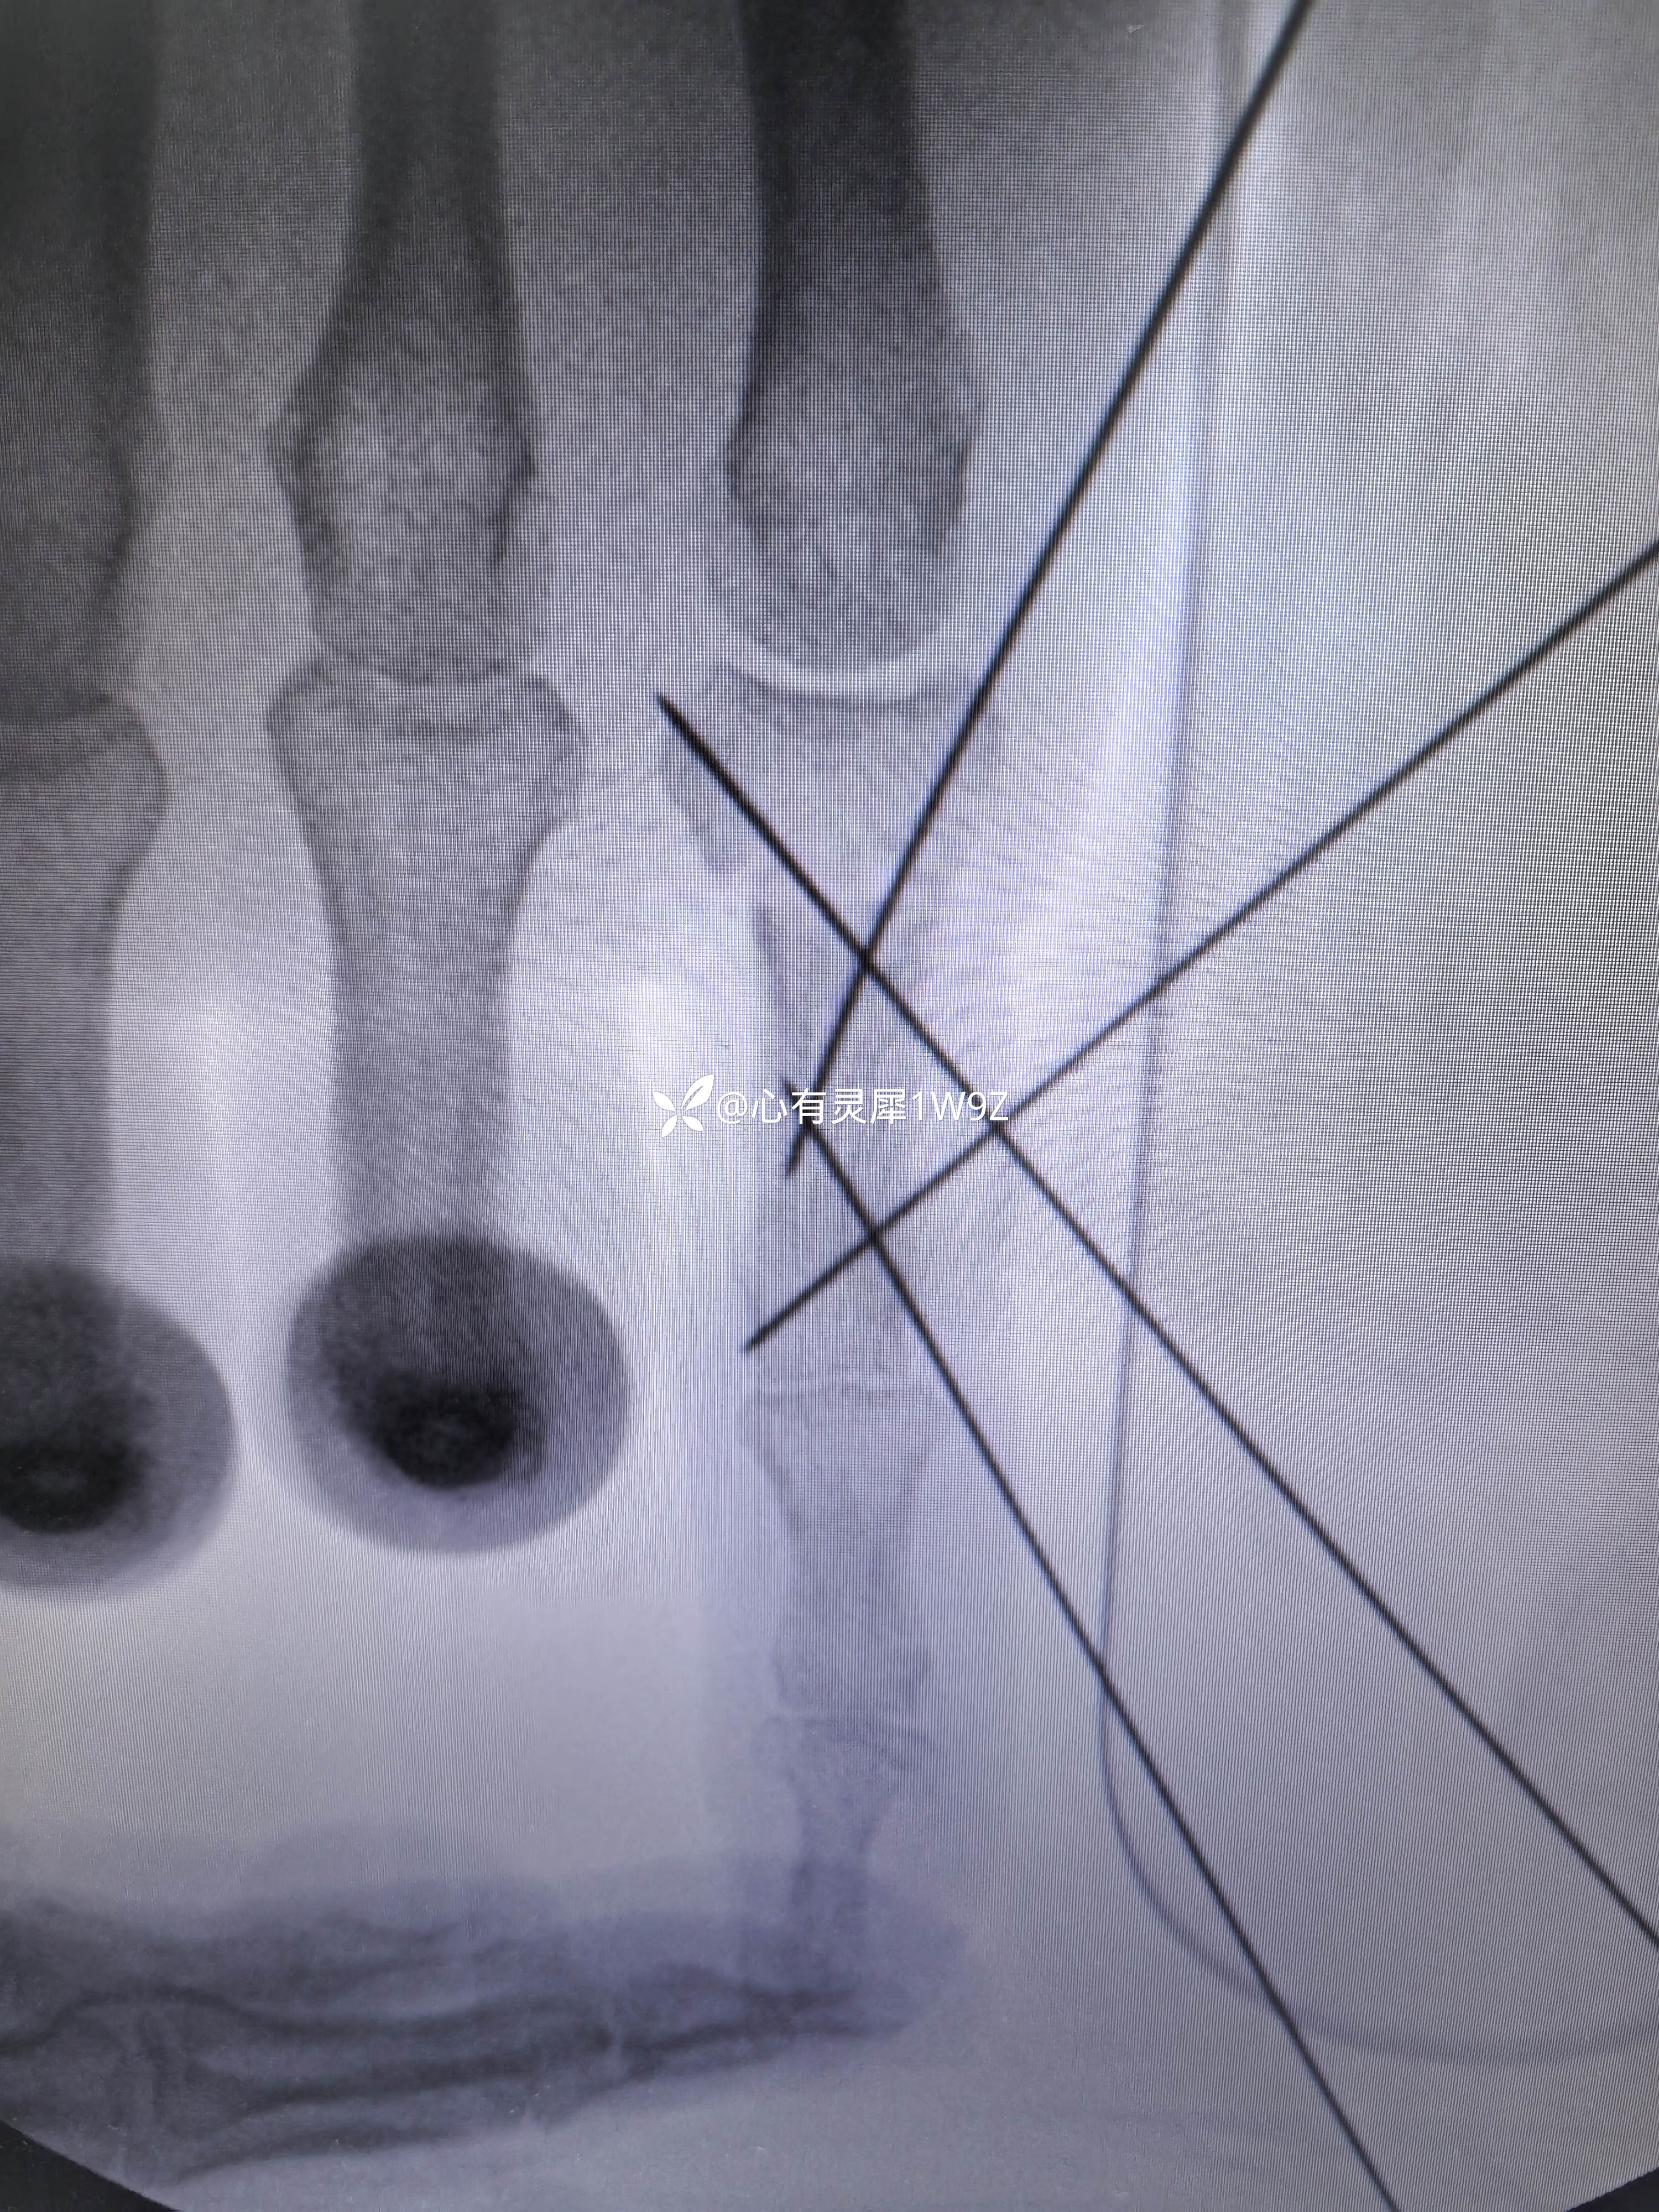

小指近节指骨两处骨折

【治疗经过及结果】: